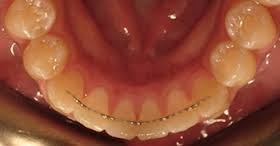

Dişlerde, ortodontik tedavinin bitiminden hemen sonra pozisyonlarını değiştirme ve tedavinin başındaki ilk konumuna geri dönme eğilimi söz konusudur. Bu nedenle aktif ortodontik tedavi biter bitmez pasif ortodontik tedavi olan “pekiştirme tedavisi”ne başlanmalıdır. Bu tedavide ya dişlerin iç tarafına sabit olarak bir tel yapıştırılır ya da hastanın takıp çıkarabileceği bir pekiştirme aygıtı kullanılır. Takıp çıkarılabilen aygıtın hekimin talimatlarına uygun olarak kullanılması tedavi sonucunun kalıcılığı açısından çok önemlidir.